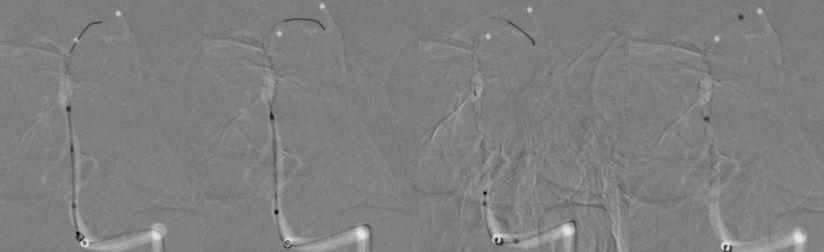

1、患者全身麻醉,右侧股动脉穿刺置入8F动脉鞘,5F中间导管携带6F长鞘超选入左侧椎动脉,行造影及三维旋转寻找最佳工作角度(图8)。

图8

4、支架完全释放后造影可见支架完全覆盖动脉瘤,贴壁良好,载瘤动脉及支架覆盖的双侧AICA及右侧椎动脉通畅(图11)。

图11